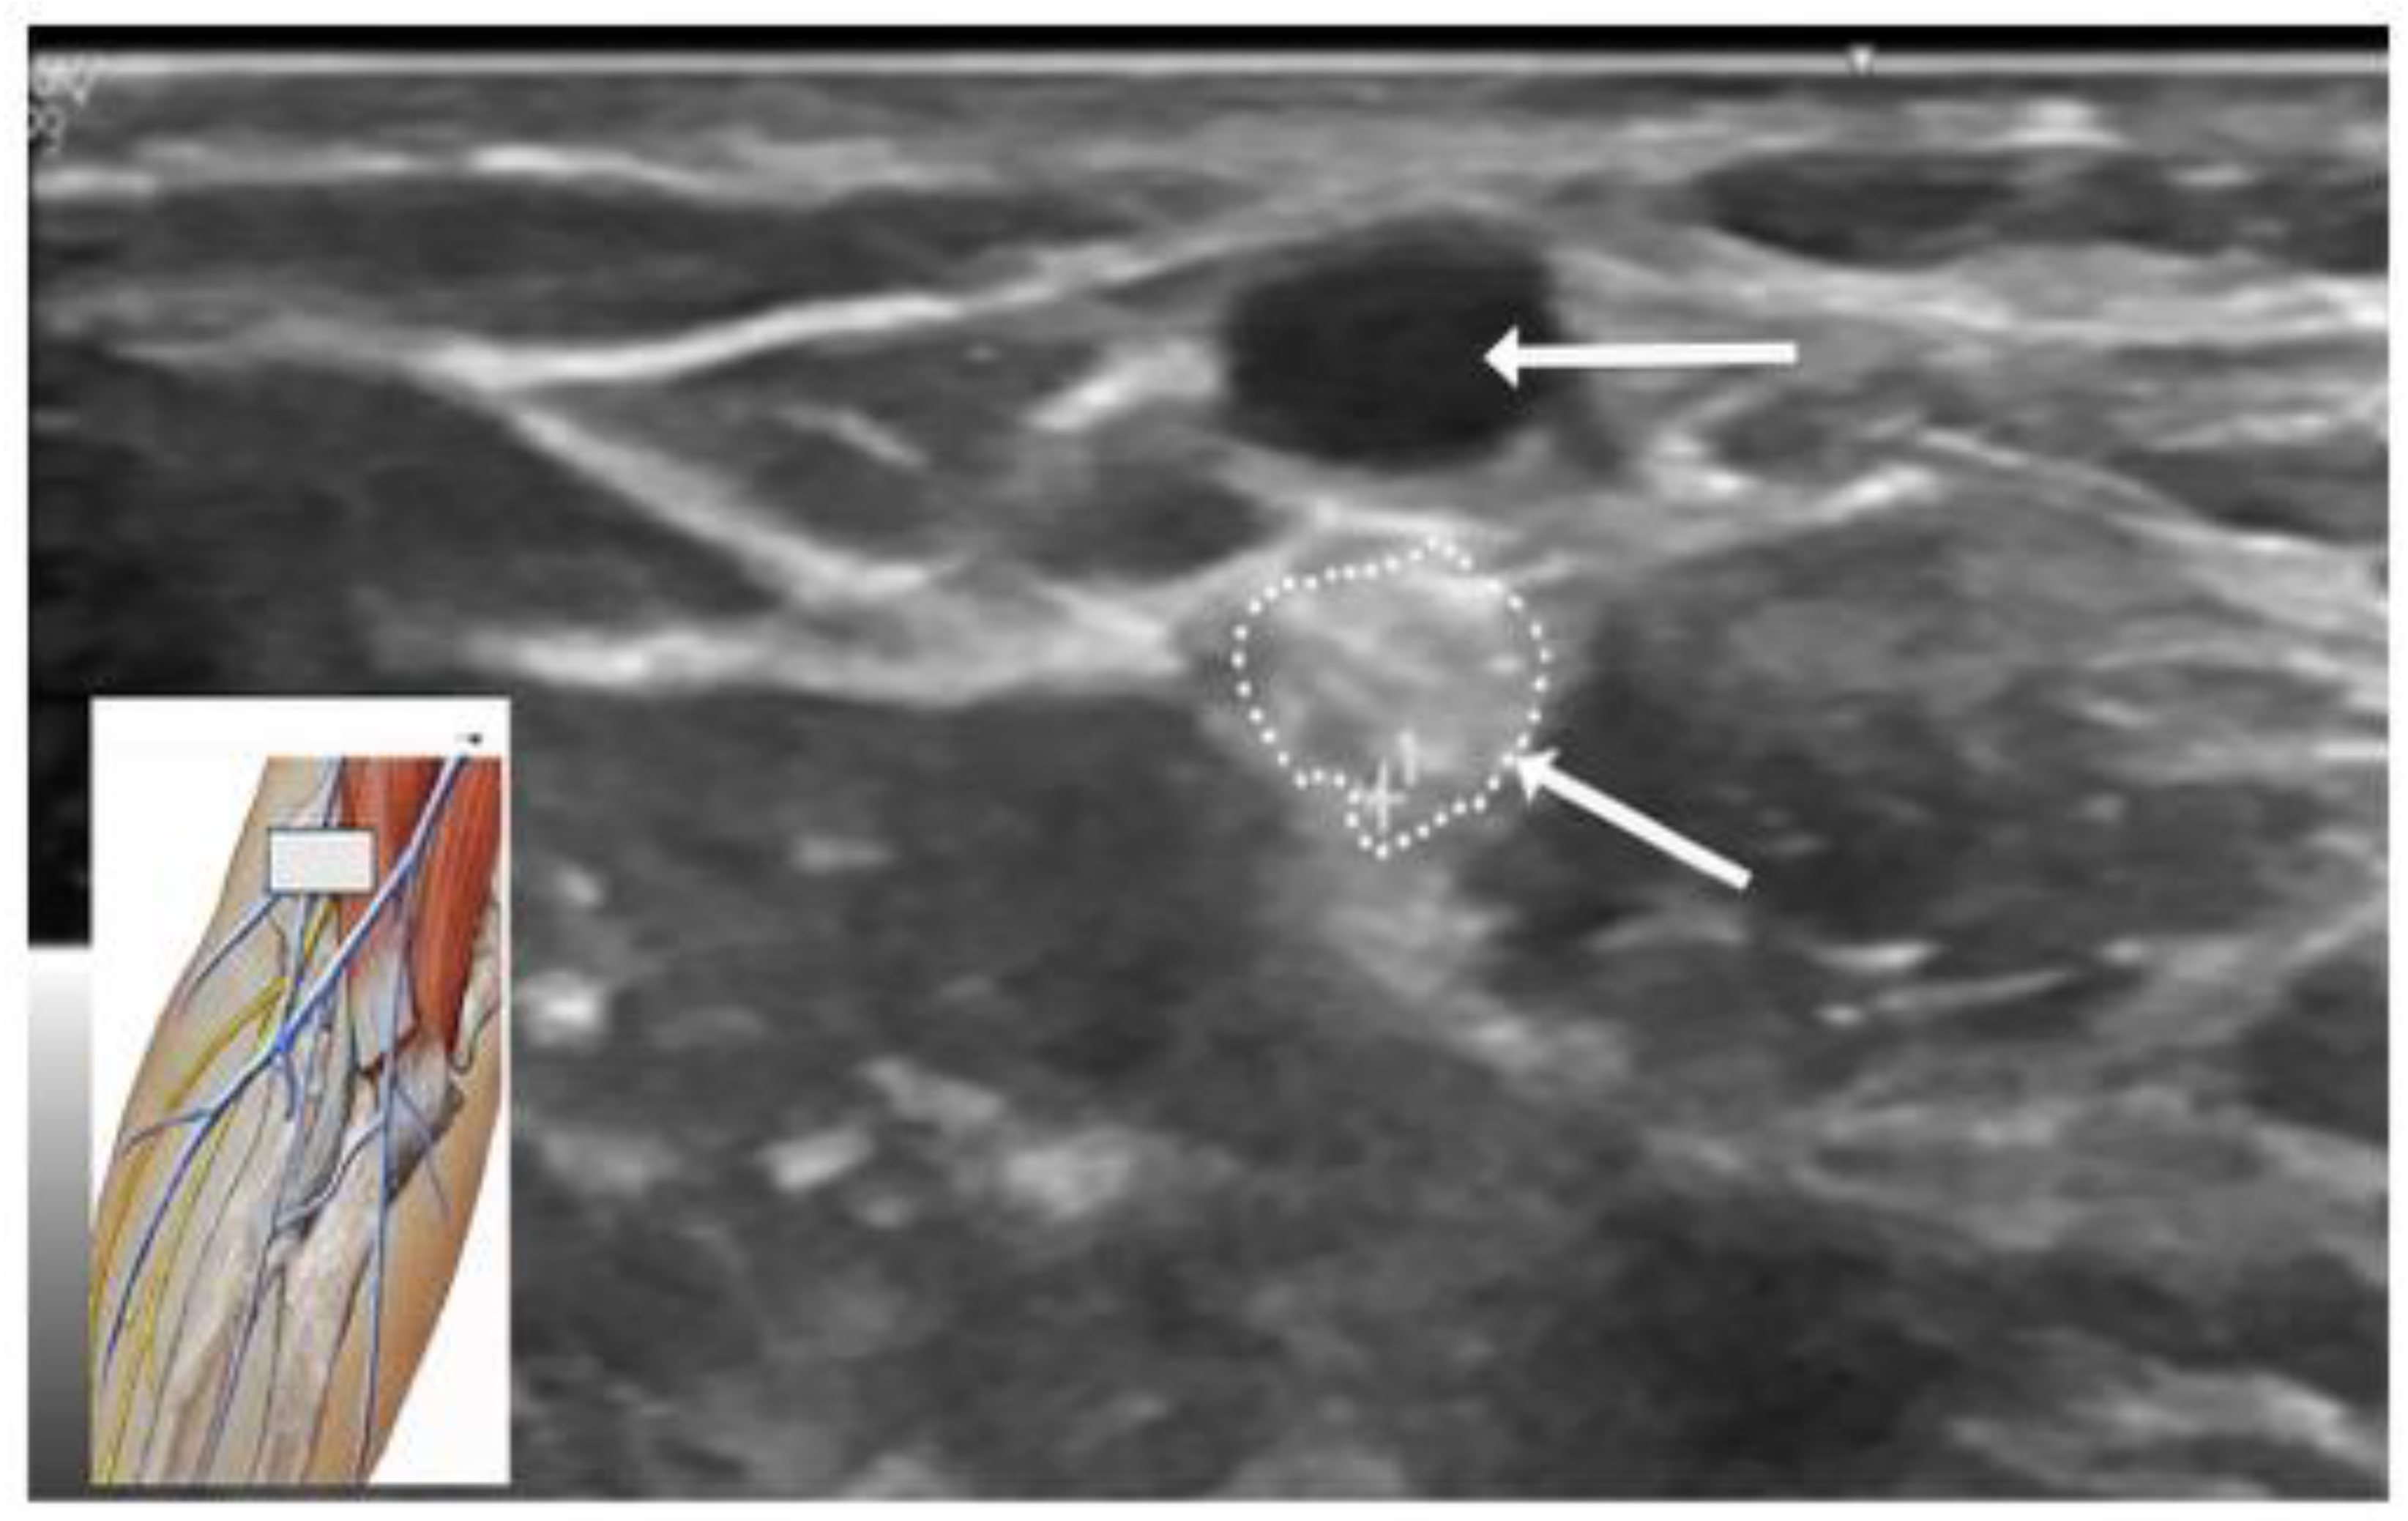

4.5. Ultrasound Studies

US studies may assist in the diagnostic evaluation of LACN neuropathy by differentiating various conditions with symptoms involving the upper arm, elbow, forearm, and wrist [35]. US has important role in the localization and determining the etiology of LACN neuropathy. In Chiavaras and colleagues’ study of US of the LACN with MRI and anatomic correlation in 13 patients with LACN neuropathy, the symptomatic LACN demonstrated fusiform enlargement, increased echogenicity, and loss of the normal fascicular echotexture [35]. The mean cross-sectional area of the symptomatic LACN was 12.0 mm2 compared to 3.3 mm2 at the same level in the contralateral normal side. While only 7 patients in our series underwent an US study, it was valuable in providing details of the masses in the upper extremity compressing the LACN. Figure 4 depicts the US study involving injury to the LACN from phlebotomy.

Figure 4. Ultrasound of injury to the lateral antebrachial cutaneous nerve from phlebotomy. Horizontal arrow points to the cephalic vein. Oblique arrow points to enlarged and hyperechoic lateral antebrachial cutaneous nerve.